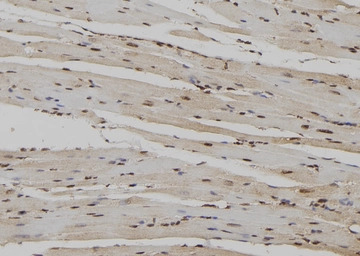

IHC-P analysis of mouse heart tissue section using GTX00625 RyR2 (phospho Ser2808) antibody.

Antigen retireval : Heat mediated antigen retrieval step in citrate buffer

Dilution : 1:100